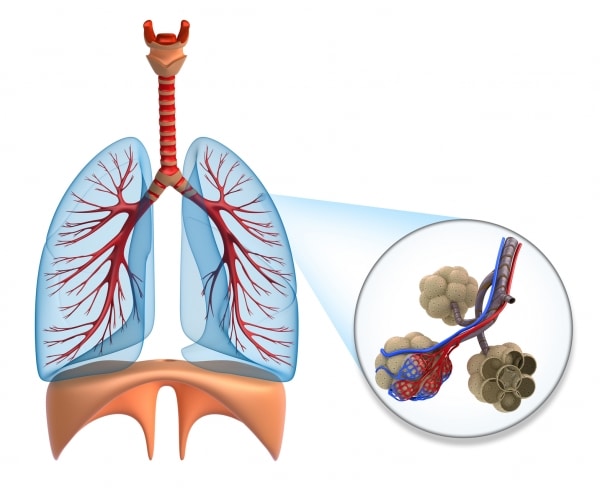

Crois-le ou non, ton corps n’utilise même pas le quart de l’air inspiré par les poumons. Quel gaspillage ! Mais tu n’as pas vraiment le choix : l’air est constitué de 78 % d’azote, de 21 % d’oxygène et de quelques autres gaz plus rares. Seul l’oxygène est essentiel à notre survie. L’azote ne peut pas traverser les capillaires. Il reste dans les alvéoles et est rejeté lors de l’expiration. L’oxygène passe quant à lui directement de tes poumons à ton sang en traversant de minuscules vaisseaux sanguins, les capillaires, qui tapissent la surface de tes poumons. C’est là que les globules rouges entrent en action. Ton sang est rempli de ces minuscules cellules qui transportent l’oxygène vers chacune des cellules de ton corps à travers le système sanguin.

Après avoir utilisé l’oxygène que le sang leur amène, tes cellules rejettent un déchet : le gaz carbonique (CO2). Si tu ne t’en débarrasses pas, tes cellules mourront empoisonnées. De là l’importance de l’expiration. Empruntant le chemin inverse de celui de l’oxygène, le gaz carbonique est transporté par le sang vers tes poumons. Il traverse les capillaires, puis il est rejeté par ta bouche ou ton nez.